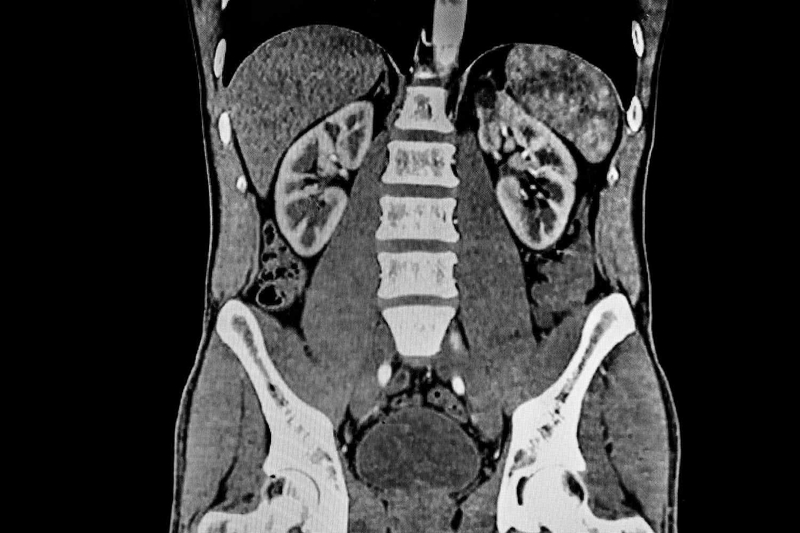

Chụp CT thận ứ nước là kỹ thuật chẩn đoán bệnh thông qua hình ảnh. Bằng cách chụp lại tình trạng của hai quả thận, đài thận, cuống thận và xương thận, các bác sĩ có thể phát hiện kịp thời dấu hiệu hệ thống thoát nước bị giãn nở bất thường. Nguyên nhân là do chức năng lọc máu của thận bị suy giảm, nước tiểu đọng lại bên trong thận gây tắc nghẽn đường tiết niệu.

Nhiều nghiên cứu đã chỉ ra rằng, kỹ thuật chụp cắt lớp vi tính cho độ nhạy khoảng 84.8%, độ đặc hiệu ở mức 70.8%. Nếu tình trạng thận bị ứ nước bắt nguồn từ sự tắc nghẽn đường tiết niệu, hình ảnh chụp CT sẽ xuất hiện các đặc điểm sau: